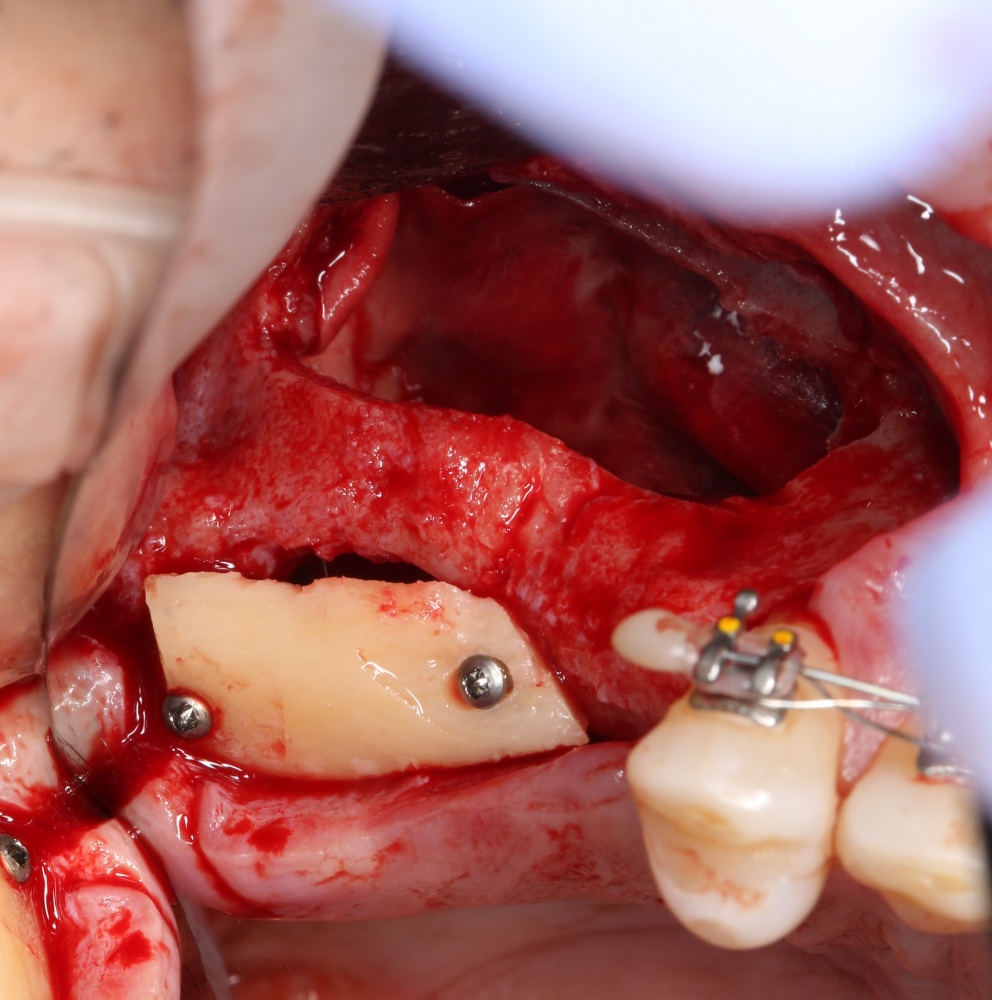

Кстати, обрати внимание на ширину альвеолярного гребня (левая картинка). Она чуть меньше 3 мм. Это объясняет, почему я засомневался в возможности установки имплантатов одновременно с остеопластикой. Понятно и без КЛКТ.

Для получения костного блока, мы открываем донорскую зону, наружную косую линию нижней челюсти.

Для получения костного блока мы использовали ультразвуковую пьезохирургическую систему. Это самый удобный и безопасный инструмент для проведения подобных манипуляций. С помощью него мы сформировали и выделили костный блок. Он должен отделяться легким движением остеотома или элеватора. Как это сделать правильно — читай здесь>>

Подготовка костного ложа и фиксация аутотрансплантата

Возвращаемся к основной операционной области. Еще раз посмотрим на альвеолярный гребень, поофигеваем от его ширины и моих грандиозных планов:

Я зафиксировал костный блок практически без адаптации на несколько винтов. Обрати внимание, что винты находятся в зоне, где не планируется установка имплантатов. Фиксация должна быть надежной, поскольку мне еще предстояла подготовка лунок для имплантатов. Трех винтов для этого вполне достаточно.

Дальнейшая адаптация костного блока свелась к сглаживанию острых краев. После чего я приступил к подготовке лунок и установке имплантатов.

Установка имплантатов.

Напомню, что для этой работы я выбрал субкрестальные имплантаты Ankylos C/X. Они прекрасно сочетаются с любым методом остеопластики.

Я не планирую установку супраструктур или коронок, поэтому на уровень первичной стабильности можно положить болт. Даже наоборот — чем меньше крутящий момент при установке, тем лучше. Для имплантатов Ankylos и подобных им, это особенно важно. В общем, момент силы при установке — не более 10-15 Нсм.

Ремарка: имплантаты с предустановленными имплантодержателями хороши тем, что с ними легко контролировать позиционирование имплантатов. В случае с Ankylos С/Х - еще и крутящий момент. Имплантодержатель должен отсоединяться от имплантата с легким щелчком. Если его клинит, и тебе приходится прикладывать для этого усилия, то ты, однозначно, превысил момент силы во время установки имплантата. Следовательно, жди проблем.

Глянем на то, что получилось: